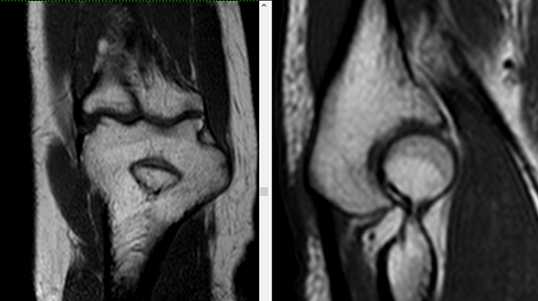

МРТ локтевого сустава в корональной плоскости. В подкожно-жировой клетчатке локтевого сустава отмечаются множественные образования неправильной вытянутой формы, местами сливающиеся между собой — вероятно, венозная мальформация.

МРТ локтевого сустава в сагиттальной плоскости. Отмечается повышенное скопление свободной синовиальной жидкости в полости локтевого сустава. Синовиальная оболочка умеренно гипертрофирована.

б)МРТ локтевого сустава в корональной плоскости. Общее сухожилие разгибателей в месте прикрепления к латеральному надмыщелку плечевой кости неравномерно утолщено, МР-сигнал от него неоднородно повышен на PD FS-ВИ и Т2-ВИ за счет выраженного отека и разволокнения (признаки латерального эпикондилита), общая целость его не нарушена. Окружающие мягкие ткани с признаками отека.